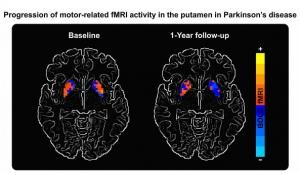

Actualité publiée le 02/09/2016PARKINSON: Un biomarqueur non-invasif évident de l'efficacité du traitement?

Actualité publiée le 25/08/2016